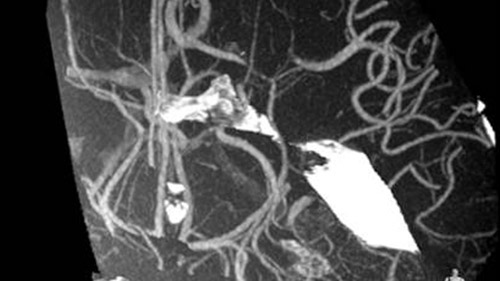

VasoCT visualizes small intra-cranial devices in vessel context with unmatched spatial resolution. Metal Artifact Reduction decreases streaking artifacts as from coil mass close to intra-cranial devices.

VasoCT (Allura X-ray system with dedicated EPX settings + XperCT + intravenous contrast injection) provides high-resolution imaging of intracranial arteries to help visualize location, size, and direction of an occlusion in case of Ischemic Stroke.

MR/CT Roadmap visualizes lesion boundaries and corresponding vascularization, while helping you to manage X-ray dose and contrast medium. 3D Roadmap provides full 3D view for dynamic guidance of guidewire and catheter navigation through complex vascular lesions.